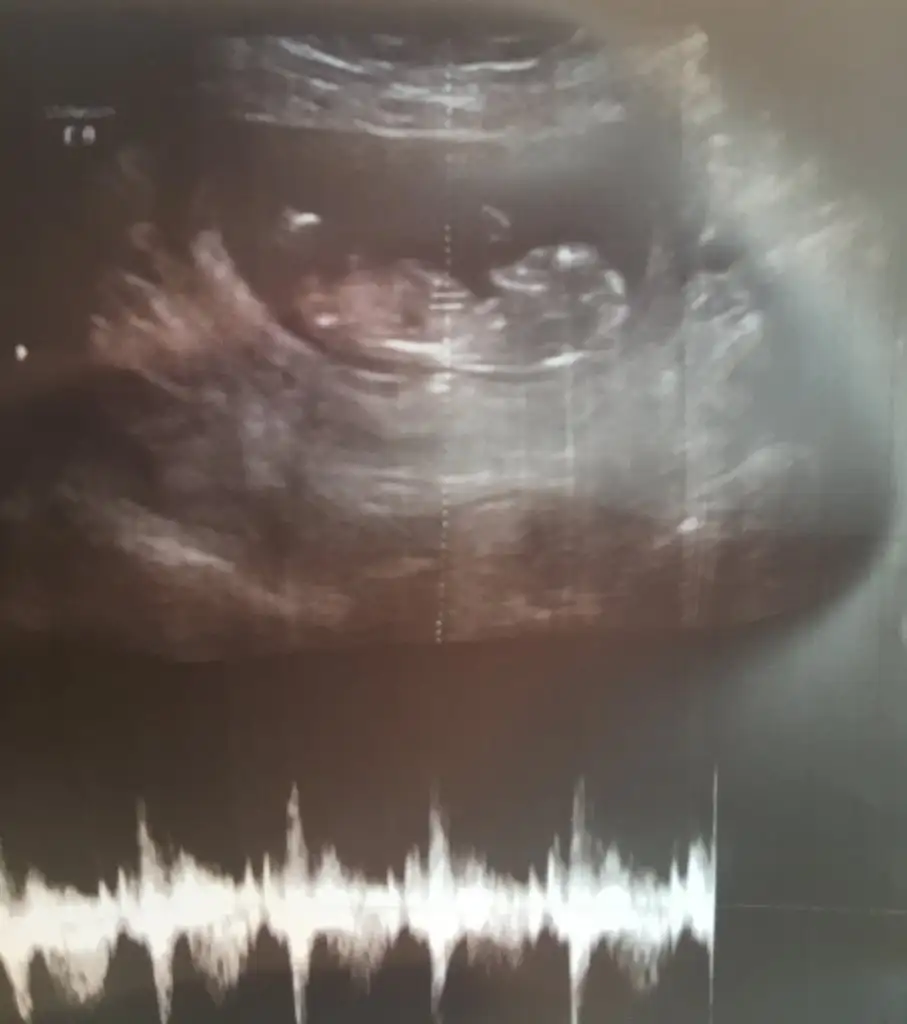

Kıza benzettim ben canımKızlar nasipse bende mart annesi olacağım. Son adet tarihime göre 12+0 haftalık ama bugün ikili tarama için gittim 12+4 haftalık çıktı bunlarda görüntüleri. Sizce cinsiyeti nedir nub anlayan var mı

Pek emin olamadım ama erkek gibi geldi, sağlıkla gelsin inşallahKızlar nasipse bende mart annesi olacağım. Son adet tarihime göre 12+0 haftalık ama bugün ikili tarama için gittim 12+4 haftalık çıktı bunlarda görüntüleri. Sizce cinsiyeti nedir nub anlayan var mı